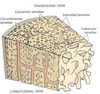

Describe the microanatomy of bone

- Cortical bone is made of parallel osteons

- Osteons are 0.2mm in diameter

- They have a central canal in the middle called the Haverisan canal which contains veins, arteries and a mechanosensory network

- Circumferential lamellae surround the whole bone at the periosteum

- Interstitial lamellae are found between the osteons

- Trabecular canals are organised in layers